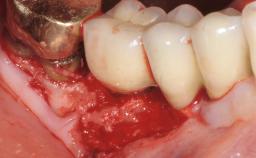

Mauricio Araujo and Flauvia Matarazzo present this straightforward clinical case, demonstrating the potential effect of implant placement depth on the resolution of peri-implant treatment. A 42-year-old systemically healthy female patient, a non-smoker with no history of periodontitis, was treated at the Dental Clinic at the State University of Maringá, Brazil between 2008 and 2009, when she received five implants restored with single crowns at sites 14, 26, 27, 36, and 46. After delivery of the implant-supported prosthetic restorations, the patient was enrolled in the supportive peri-implant therapy (SPiT) maintenance program at the same university.